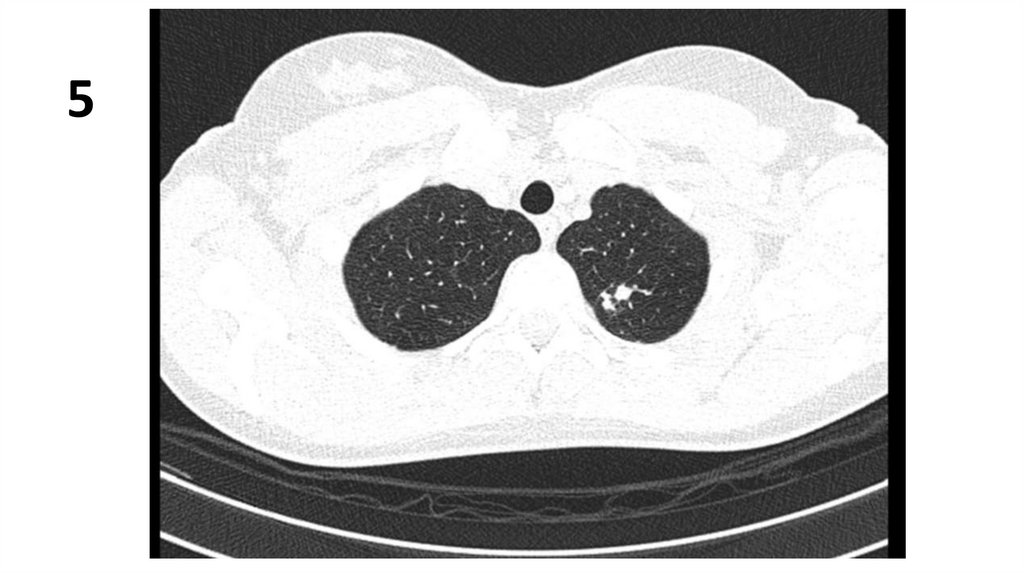

5.

4

6.

5